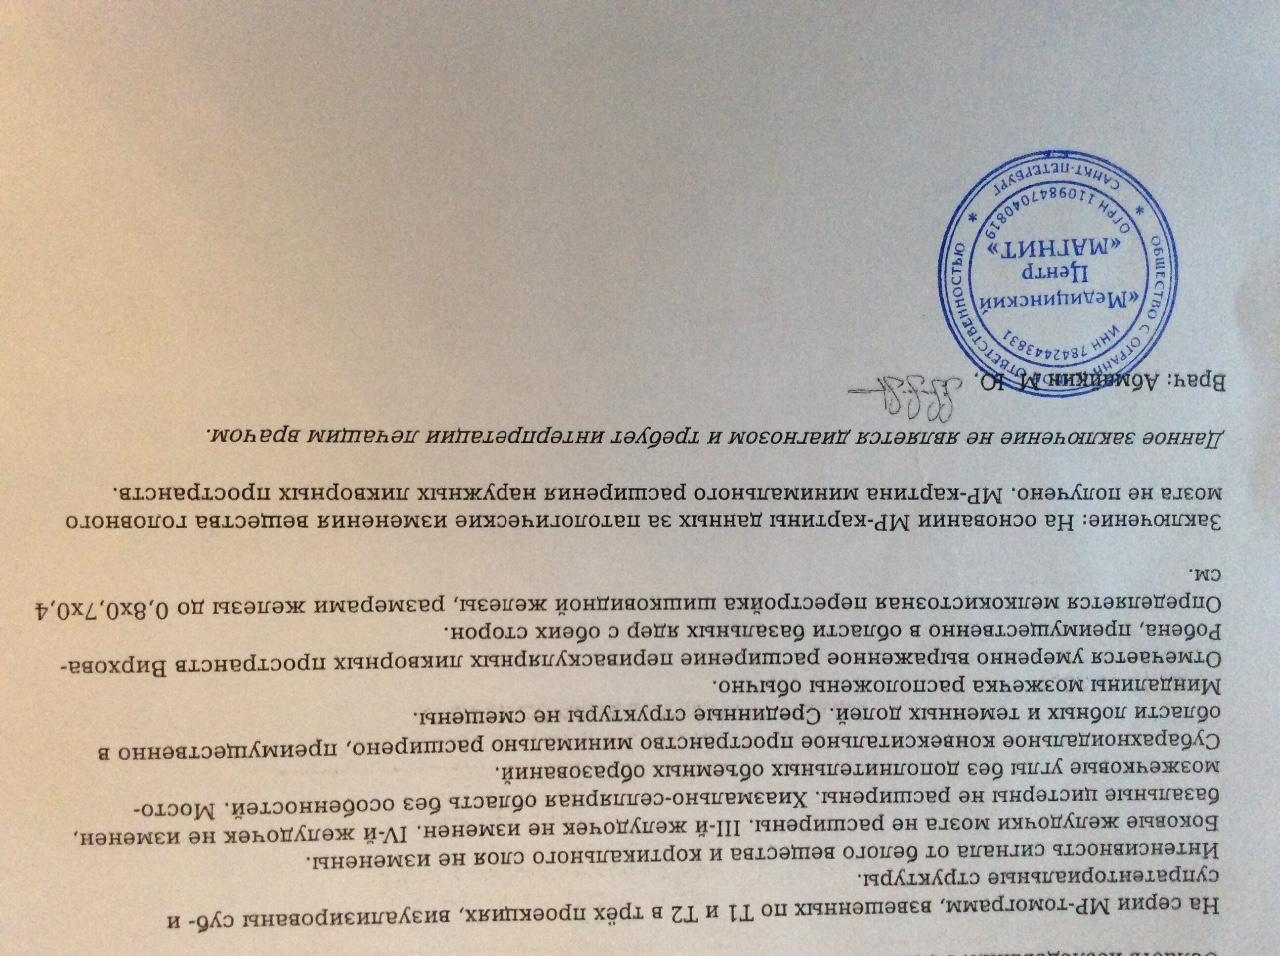

Признаки умеренно выраженной наружная

Признаки умеренно выраженной наружная 113 фото